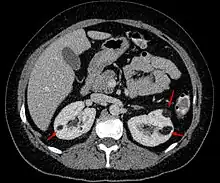

| Angiomyolipoma in both kidneys (arrows) in computer tomography. The tumours are hypodense (dark) due to fat content. | |